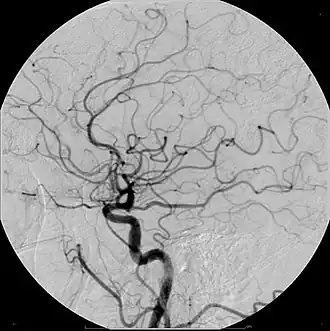

Digitale subtractieangiografie of DSA is een angiografische techniek die wordt gebruikt in de interventieradiologie. Met deze techniek worden duidelijke afbeeldingen van bloedvaten gemaakt in een omgeving met veel botstructuren of andere weefsels met een hoge dichtheid. De gemaakte afbeelding wordt een angiogram genoemd.

De afbeeldingen worden gemaakt door gebruik te maken van contrastmiddel, waar meestal jodium aan is toegevoegd. Eerst wordt voor toediening van dit middel een precontrast röntgenfoto gemaakt. Hierna wordt het contrastmiddel toegediend en opnieuw een foto gemaakt. Door vervolgens beide afbeeldingen van elkaar af te trekken, blijft alleen het verschil tussen beide afbeeldingen, namelijk de structuur van de bloedvaten met het contrastmiddel over.

DSA wordt gebruikt om bloedvaten af te beelden. Het is te gebruiken bij afsluitingen van slagaders en aders, zoals bij carotisstenose, longembolieën en acute ischemie van de ledematen. Het heeft ook een rol bij het afbeelden van cerebrale aneurysmata en arterioveneuze malformaties.